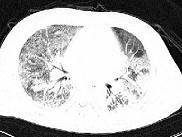

问题 男性,42岁,近2年来无明显诱因反复出现咳嗽,痰少,活动后气促,无发热,无胸痛,无咯血,心电图及心脏彩超未见异常,肺功能FEV1.901,FVC2.001,DLco下降,支气管激发试验阴性。胸部CT见图,该患者最有可能是下列哪一种疾病 ( )

选项 A.支气管哮喘 B.慢性阻塞性肺疾病 C.支气管扩张 D.支气管肺癌 E.特发性间质性肺炎

答案 E